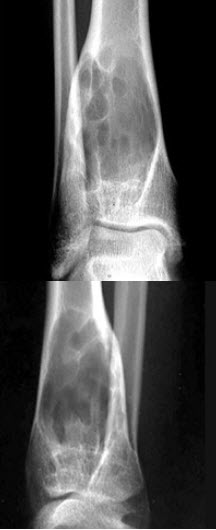

51、单项选择题

女,26岁,右踝部疼痛,结合图像,最可能的诊断是()

A.单纯性骨囊肿

B.骨巨细胞瘤

C.嗜酸性肉芽肿

D.骨纤维异常增殖症

E.动脉瘤样骨囊肿